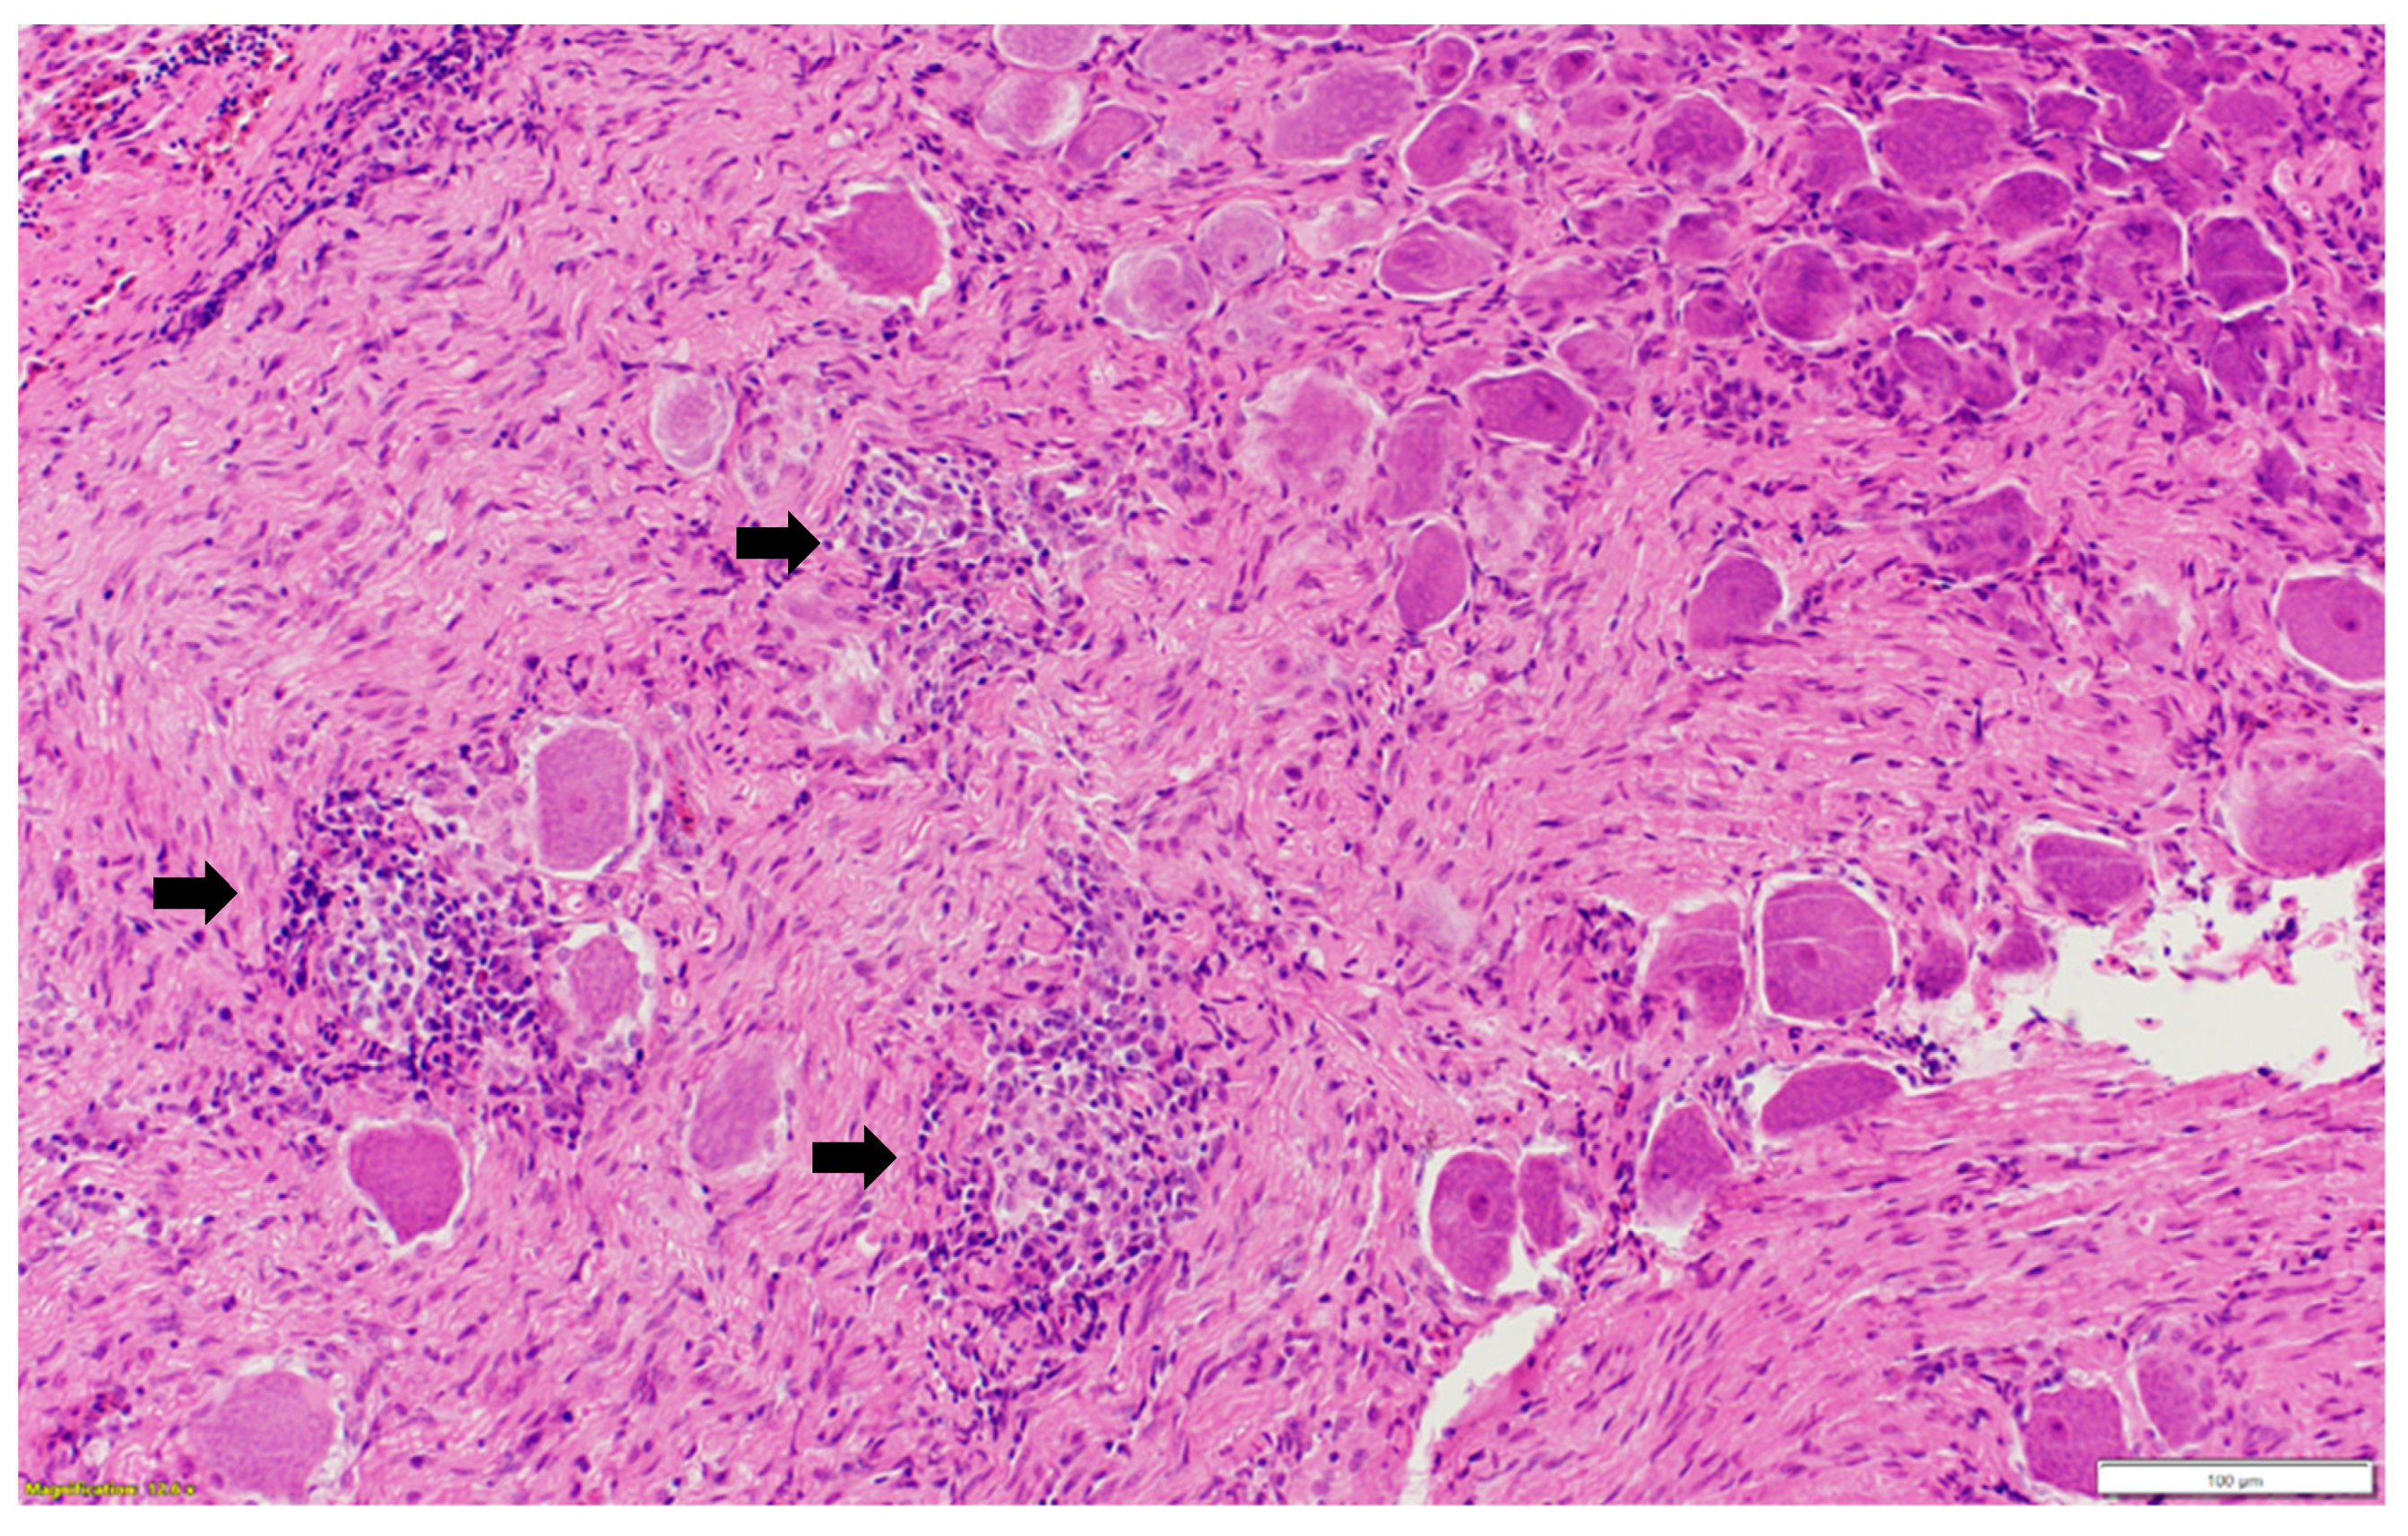

Microscopic examination of different brain, spinal cord, peripheral nerves, and ganglions sections revealed multifocal areas of lymphoplasmacytic and histiocytic infiltrates, indicating encephalitis (Figure 1) in the cerebral white matter, thalamus, hippocampus, and medulla oblongata close the ventricular space. The inflammatory cells around the vessels (perivascular cuffing) as well as around the neurons (satellitosis and neuronophagia) resulted in several neuronal degeneration and central chromatolysis (Figure 2). The gray matter in the spinal cord had multifocal lymphoplasmacytic infiltrates, indicating myelitis (Figure 3). In addition, there was mild to moderate multifocal ganglioneuritis in the pelvis ganglions (Figure 4).

Figure 4. Multifocal inflammatory cellular infiltration (black arrow) among the ganglionic neurons (ganglioneuritis) in the pelvic ganglion. Paraffin-embedded tissue was stained with hematoxylin and eosin.